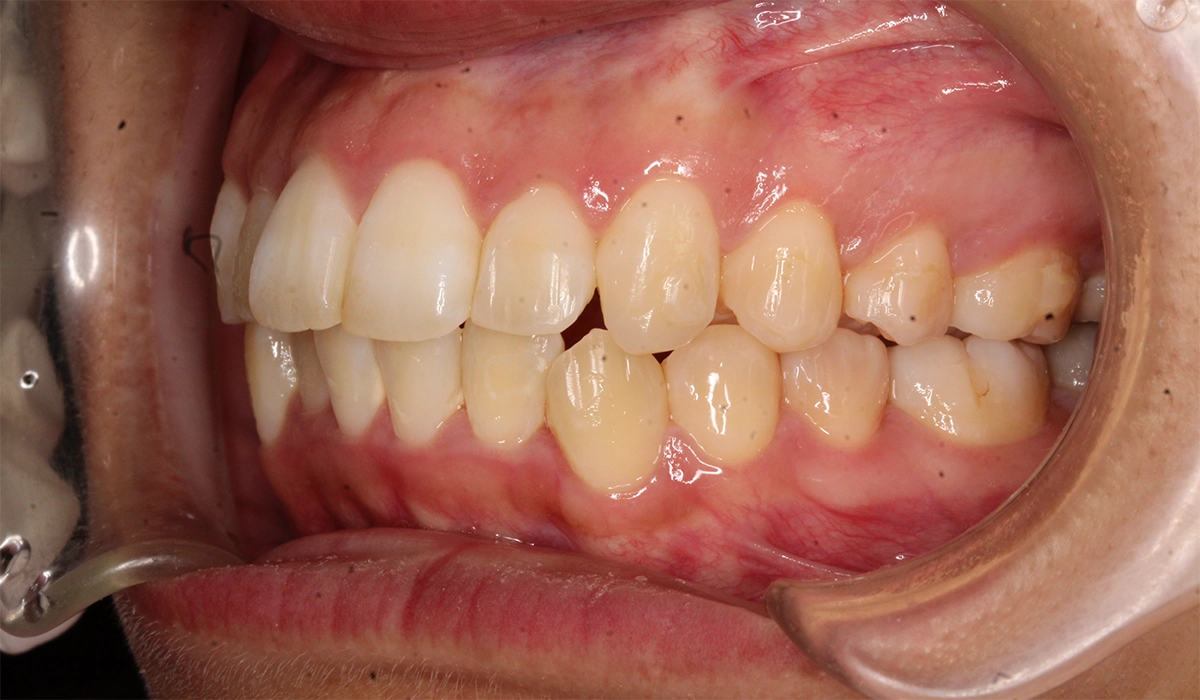

術後:右側